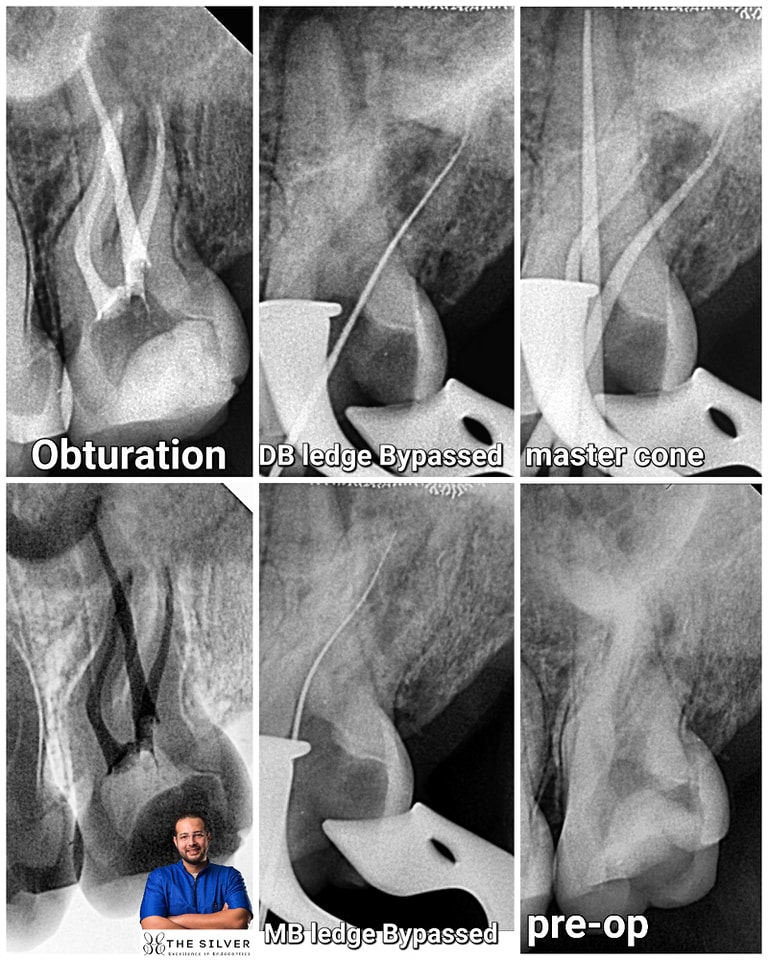

Pre-op

MB ledge Bypassed

DB ledge Bypassed

Palatal canal WL

Master Cone

Obturation